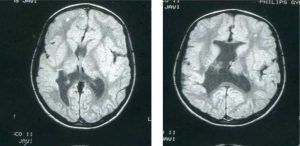

What is Schizencephaly? Schizencephaly is a rare congenital cerebral malformation characterized by linear clefts in […]